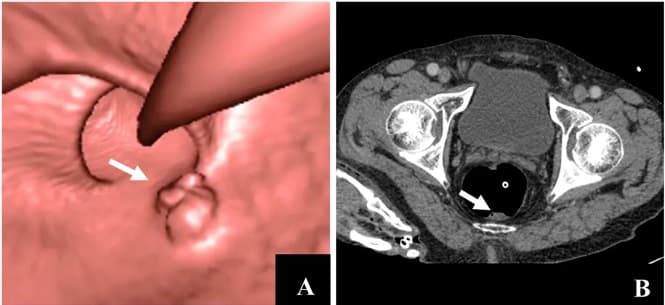

Virtual colonoscopy (VC, also called CT colonography or CT pneumocolon) is the use of CT scanning or magnetic resonance imaging (MRI) to produce two- and three-dimensional images of the colon (large intestine), from the lowest part, the rectum, to the lower end of the small intestine, and to display the images on an electronic display device. The procedure is used to screen for colon cancer and polyps, and may detect diverticulosis. A virtual colonoscopy can provide 3D reconstructed endoluminal views of the bowel. VC provides a secondary benefit of revealing diseases or abnormalities outside the colon. While preparations for VC vary, the patient will usually be asked to take laxatives or other oral agents at home the day before the procedure to clear stool from the colon. A suppository is also used to cleanse the rectum of any remaining fecal matter. The patient may also be given a solution designed to coat any residual faeces which may not have been cleared by the laxative, called 'faecal tagging'. This allows the physician (usually a consultant radiologist), viewing the 3D images to effectively subtract the left-over faeces, which may otherwise give false positive results. VC takes place in the radiology department of a hospital or medical center. The examination takes about 10 minutes and does not require sedatives. During the procedure: The patient is placed in a supine position on the examination table The patient may be given a dosage of Butylscopolamine intravenously to minimize muscle activity in the area. A thin tube is inserted into the rectum, so that air can be pumped through the tube in order to inflate the colon for better viewing. The table moves through the scanner to produce a series of two-dimensional cross-sections along the length of the colon. A computer program puts these images together to create a three-dimensional picture that can be viewed on the video screen. The patient is asked to hold his/her breath during the scan to avoid distortion on the images. The scan is then repeated with the patient lying in a prone position.